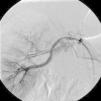

Non-invasive 24-hour blood pressure monitoring revealed stage I hypertension (mean daytime blood pressure 156/87mmHg). Hormonal and imaging studies were also performed for etiologic diagnosis of his hypertension, as well as a captopril test, which was positive for renovascular hypertension. Following this result, renal angiography was performed, which revealed, bilaterally, two renal arteries, and in addition, to the right, depending on the superior artery, three saccular aneurysms 14mm, 6mm and 3.5mm in size. The largest aneurysm appeared to compress the lower polar artery (Figure 1). The aneurysms were treated with placement of a polytetrafluoroethylene (PTFE)-coated stent, in order to prevent expansion and rupture of the aneurysms and to treat the hypertension. Digital subtraction angiography was performed using a right femoral approach. A 65cm 4F sheath was introduced, and the right renal artery was engaged with a 4F Cobra catheter and a 0.014-inch hydrophilic guidewire. Aneurysm morphology was assessed using conventional angiography and flat-panel computed tomography. Stent diameter and length were determined from a three-dimensional flat-panel rotational angiography data set. After administration of 5000 IU of heparin, the aneurysm was crossed with the guidewire and catheter. The wire was exchanged through the same catheter with a 0.014-inch guidewire. Finally, a 6×22-mm covered Atrium stent was deployed, bridging the aneurysm and covering the artery, resulting in successful exclusion of the aneurysms (Figures 2 and 3). The patient was admitted the day before the procedure and was discharged the day after, medicated with 100mg aspirin and 75mg clopidogrel/day, as dual antiplatelet therapy. Ten months after the procedure the patient was asymptomatic, with normal blood pressure and without antihypertensive therapy.

The procedure was uneventful and the final images show the successful exclusion of the aneurysms. Ten months after the procedure, the absence of symptoms and normalization of blood pressure show the success of the intervention.